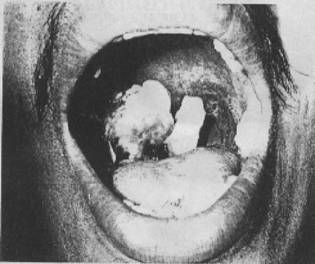

แอนแทรกซ์ในปากและคอหอย

ติดโดยการกินเช่นเดียวกับแอนแทรกซ์ที่ทางเดินอาหาร ผู้ป่วยจะแสดงอาการเจ็บคอ คอบวม แข็งตึง และกลืนอาหารลำบาก เพราะมีแผลเนื้อตายที่คอและคอหอย (รูปที่ 7)